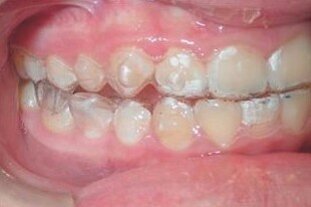

Upper and lower Invisalign aligners with the new precision wings feature engaged, and the mandible advanced to an edge-to-edge position.

ClinCheck® set-up of aligner stage #1, with mandibular advancement features (precision wings) in blue.

Progress after 3 months

Progress after 6 months – notice the UL2 alignment while the bite is being corrected.

End of mandibular advancement phase after 11 months (initial aligners: U:27, L:27)

After 27 aligners in both arches (11 months of treatment, 2 weeks each aligner2), the patient was Class I canine on the right side and 3 mm Class II canine on the left. Aligner wear compliance was good and oral hygiene was excellent. The majority of the crowding in both arches was resolved during the mandibular advancement phase. The bilateral posterior open bite present would be closed by additional leveling of the curve of Spee, along with lingual root torque of the upper anterior teeth. By reducing the anterior interferences, the mandible would be able to autorotate into a better Class I relationship.